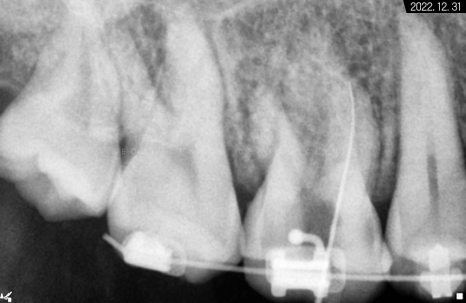

따라서 적정 시기에

CT를 촬영해 치조골 폭과 밀도를

철저하게 분석한 다음 정확한 자리를 선정하고

임플란트 식립을 진행했습니다.

하악 좌측 사랑니 발거 후

임플란트가 필요한 부분들에

픽스처를 견고하게 식립해 드렸습니다.

일정 기간이 지난 후 고정력을 체크하고

지대주에 이어서

크라운까지 예쁘게 수복해 드렸습니다~

크라운으로 감싸고 난 후의 치근단 모습입니다.

정확한 간격으로 견고하게 심어졌으며

주변 치조골 양도 풍부합니다.